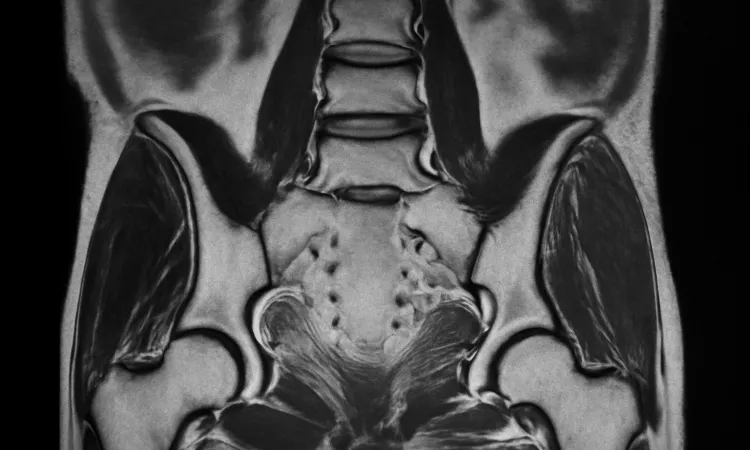

МРТ крестцово-подвздошных сочленений является ключевым инструментом диагностики, позволяющим выявить воспалительные изменения на ранних стадиях заболевания. Правильная диагностика и своевременное лечение играют важную роль в успешном управлении сакроилеитом и минимизации его последствий.

Следующим шагом является инструментальная диагностика. МРТ крестцово-подвздошных сочленений является одним из наиболее информативных методов. Этот вид исследования позволяет увидеть изменения в тканях и определить наличие воспалительных процессов. Также могут быть использованы рентгенологические исследования, которые помогают исключить другие заболевания суставов, такие как артрит или остеоартрит.